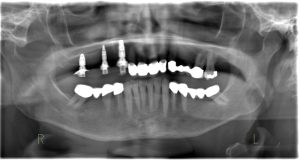

A paciente Monique, de 72 anos, apresentou-se com uma situação clássica de extremidade livre do 14 ao 17. Sua principal solicitação era o fechamento rápido e fixo do espaço esteticamente comprometido (Fig. 1). Devido a uma doença autoimune (síndrome de Sjögren), sua produção de saliva era limitada, o que reduzia a inibição natural do crescimento bacteriano oral pelo corpo e aumentava o risco de complicações na cicatrização de feridas. A paciente estava ciente desse fato e, portanto, solicitou explicitamente um procedimento cirúrgico minimamente invasivo que evitasse medidas complexas de aumento.

O diagnóstico padrão com escaneamento intraoral e CTCB (Fig. 3 escaner intraoral e Fig. 4 CTCB) mostrou disponibilidade óssea reduzida nas regiões 15 a 17, mas suficiente para a colocação imediata do implante. O dente 13, restaurado endodonticamente, apresentava uma obturação radicular que se estendia claramente além do ápice, juntamente com periodontite periapical. Em consulta com o paciente, foi decidido remover o dente.